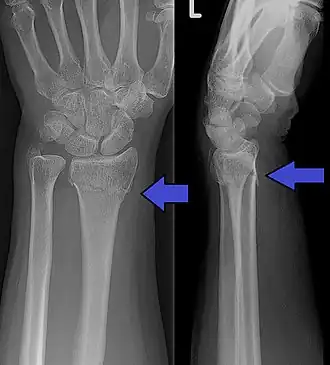

![]() Imagen radiográfica anteroposterior y lateromedial de una fractura de Colles | ||

La fractura de Colles es una fractura distal del radio. La fractura se reconoce clínicamente por la deformidad en "dorso de tenedor" debido al desplazamiento dorsal del fragmento distal del radio. Para una discusión más detallada, ver la fractura distal del radio.

Hallazgos radiológicos típicos

- Inclinación dorsal y radial de la muñeca.

- Acortamiento radial.

- Desplazamiento dorsal del fragmento distal.

- A menudo asociada a fractura del apófisis estiloide cubital.

- Ángulo volar < 10°.